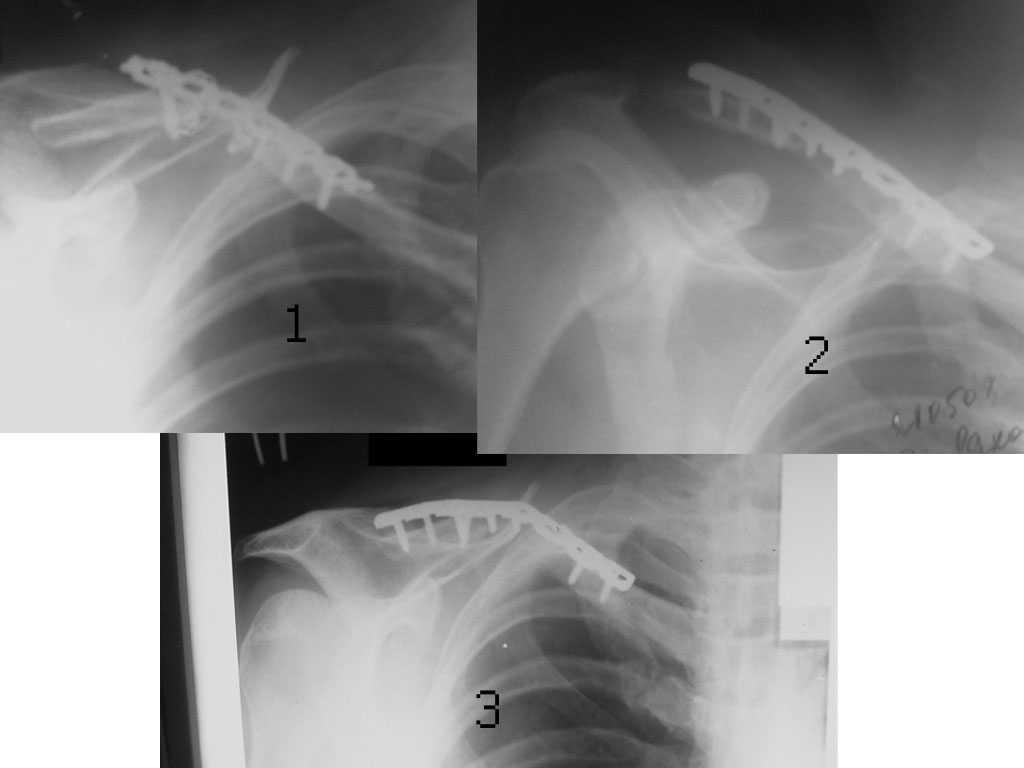

Уважаемые коллеги. Помогите с тактикой дальнейшего лечения несросшегося перелома ключицы.

В отделение поступил больной, оперированный 2 мес. назад по поводу

оскольчатого перелома средней трети правой ключицы. Перелом

несросшийся, фиксатор несостоятелен, имеется смещение, угроза

перфорации кожи. Рис. 1

Нами произведен реостеосинтез ключицы пластиной с угловой

стабильностью, с замещением деффета диафиза ключицы костным

аутотрансплантатом. Рис. 2

Через 5 мес. трансплантат рассосался, повторное смещение,

несостоятельность импланта. Рис. 3

Ваше мнение,что делать?